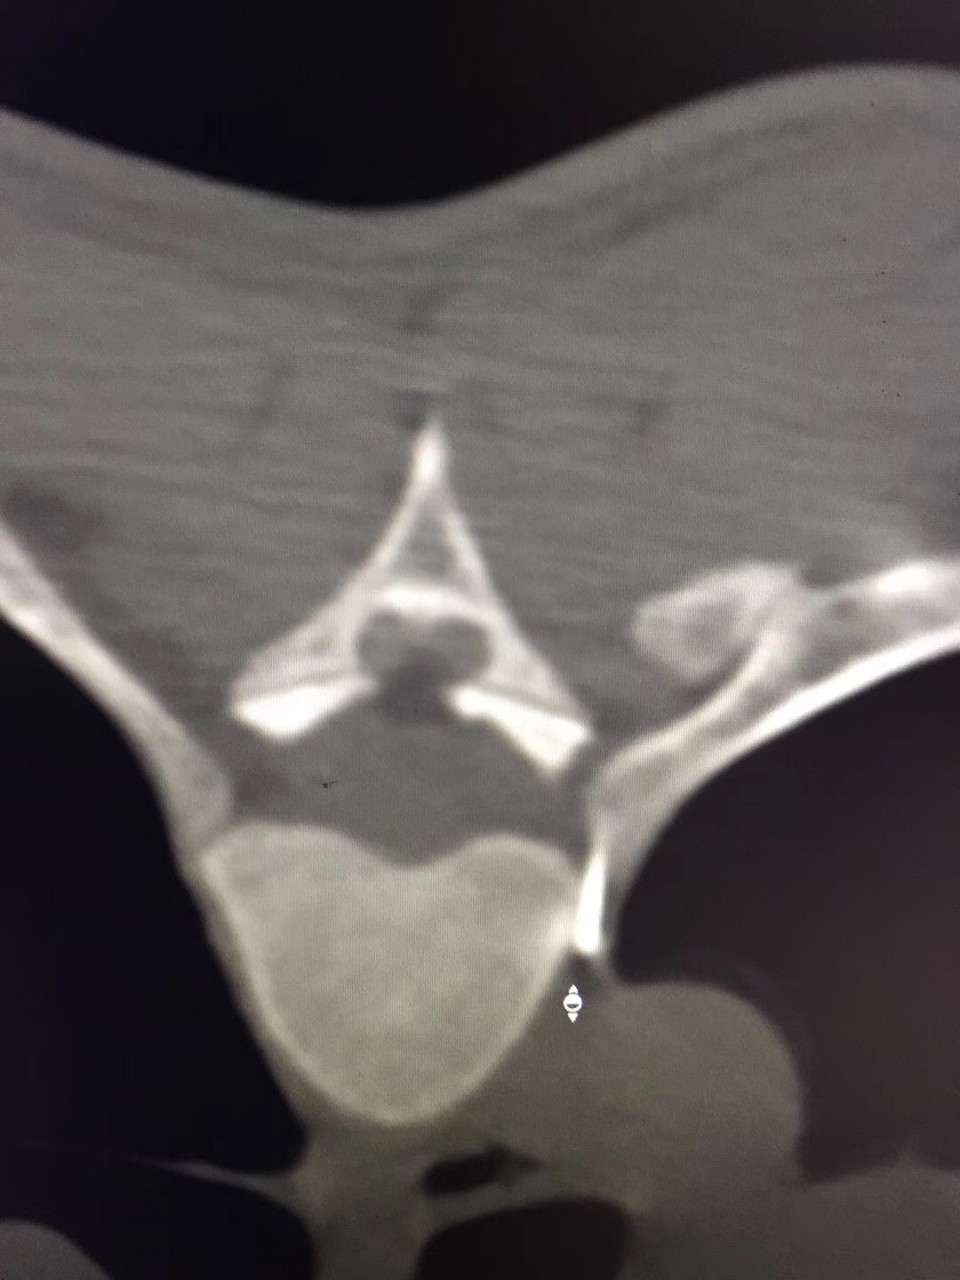

近日,疼痛科接诊了一位18岁的多汗症患者,该患者反复双足发汗多年,伴手上皮肤脱落。曾就诊于省内外多家医院,但均未获得满意的疗效。听闻安徽医科大学第一附属医院疼痛科是一种以微创介入方法治疗各种疑难病痛的科室,遂前往就诊。疼痛科副主任医师宋阳在对该患者病情特点进行综合的分析后决定对其进行CT引导下胸交感神经链无水酒精化学毁损术。当日手术结束后该患者立马感觉到双手不再是以前那样冰冷,逐渐回复了正常的温度,且发汗症状完全消失。在观察了数日之后无任何的复发症状,负责该患者的副主任医师宋阳称,通过无水酒精的化学毁损作用中断汗腺神经分泌的神经传递过程,可永久的减少出汗,达到临床治愈水平。

对于诊断明确的原发局部性多汗症患者,传统的治疗手段有局部及全身药物治疗以及激光、微波等物理疗法。目前比较主流的有CT引导下经皮穿刺胸交感神经化学阻滞及外科手术治疗。其中CT引导下交感神经链阻滞技术成功率甚至可达100%,治疗效果与胸腔镜下交感神经链切断术效果相当,应用无水酒精能达到对交感神经链的功能有效长久的阻滞,达到良好的治疗效果,且创伤更小、并发症更少。胸腔镜下交感神经切断术是治疗手、头面部及腋窝多汗症的一种二线治疗方案。但其术后疼痛、气胸、神经病变累及上肢、霍纳综合症以及代偿性多汗症发生率较高。